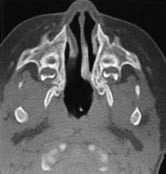

Diagnosen koanalatresi stilles gjerne ved sondering og bekreftes ved CT-bilder. Tette snitt i området nese-epipharynx gir god anatomisk kartlegging og avklarer også om andre lokale skjelettdeformiteter er til stede. Figur 1 viser anatomien ved ensidig koanalatresi. Figur 2 viser et CT-bilde ved dobbeltsidig koanalatresi.

Operasjonsmetodene er forskjellige. Noen nøyer seg med å perforere atresien og så dilatere den (8, 9). De fleste utvider den ved å fjerne det atretiske vev med bor eller stanse (2, 3, 5, 10, 11). Noen bestreber seg på å bevare slimhinnelapper, men det er svært vanskelig hos spedbarn. Laser benyttes iblant for å åpne atresien (12), men metoden har sine begrensninger (13). Best varig effekt oppnås ved at man i tillegg fjerner noen millimeter av bakre ende av vomer (3, 5). Ut fra anatomiske betraktninger (fig 1, 2) synes det hensiktsmessig, og vi har fått bedre resultater etter at vi begynte med det. Perforasjon og dilatasjon alene var ikke effektivt. For å hindre residiv må åpningen holdes åpen med en form for tamponade til såret er tilhelet. Vanligvis brukes silikonrør. Freng fikk gode resultater med å la drenene stå inne i seks uker (2). Det er ingen enighet om hvor lenge de bør stå inne. Jung benyttet seks dager (10), mens de fleste lar dem stå i 8 – 16 uker (6, 8, 14). Vi har latt dem stå i 12 uker. Så lenge de er på plass, går respirasjonen gjennom nesen uhindret. Tykkelsen på rørene er avgjørende for resultatet. Hvis de er for tykke, klemmes de sammen, nesepustingen hindres samtidig som rørene trykker mot omkringliggende vev og hindrer sårtilheling, og det disponerer for residiv.